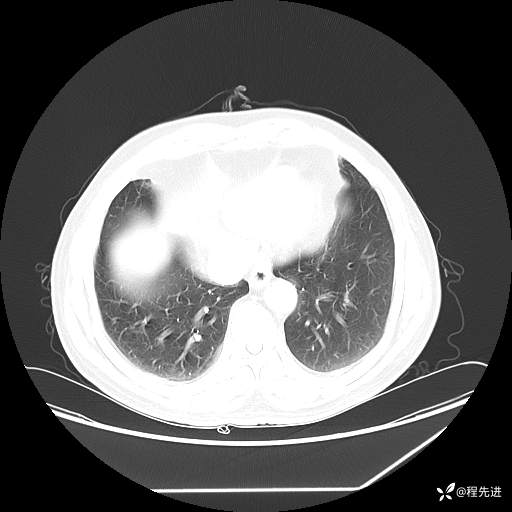

患者性别:男

患者年龄:57岁

简要病史:声嘶2月余

CT平扫+增强: